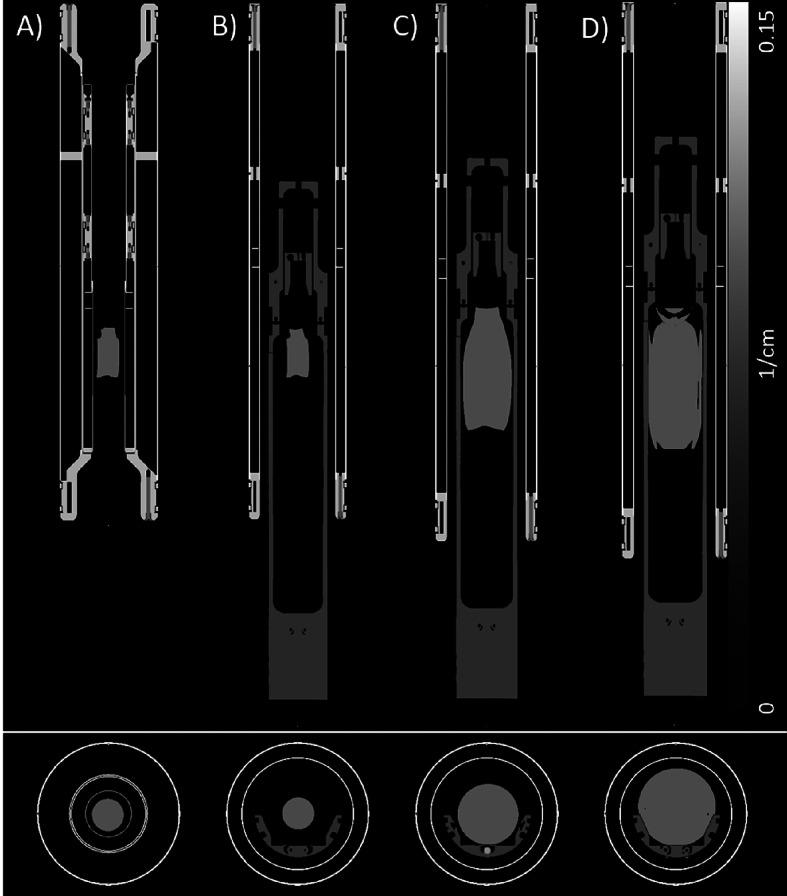

This study evaluates the performance of a positron emission tomography (PET) insert combined with a 9.4 Tesla magnetic resonance (MR) imaging system using three different radiofrequency (RF) coils. The impact of the RF coils within the PET field of view (FoV) on key PET performance parameters was carefully examined. Additionally, the accuracy of MR-based attenuation correction (AC) on the quantitative PET results was assessed.

The performance of the PET scanner was assessed according to the NEMA NU 4-2008 standards, focusing on sensitivity, spatial resolution, noise-equivalent count (NEC) rate, and image quality metrics (homogeneity, spillover ratios, and recovery coefficients). These evaluations were conducted with three different RF coils within the PET FoV: a mouse-dedicated coil, a rat-dedicated coil (not optimized for PET), and a big-rat-dedicated coil. Quantitative testing of AC accuracy was also performed using homogeneously filled phantoms of varying sizes and activity levels, comparing images reconstructed with and without AC.

The peak absolute sensitivity varied depending on the RF coil used, though spatial resolution was unaffected by the presence of the coils. The NEC curve for the mouse phantom peaked at 441.2 kcps at 29.3 MBq with the mouse-dedicated coil. For the rat phantom, NEC was only tested with the rat-dedicated coils, and the NEC peak reached 203.1 kcps at 27.5 MBq with the big-rat-dedicated coil. Activity concentrations in the NEMA image quality phantom were underestimated when standard MR-AC was applied, likely due to the absence of phantom walls in the generated µ-maps. However, for uniformly filled phantoms with wall thicknesses under 1 mm, standard MR-AC provided accurate quantification.